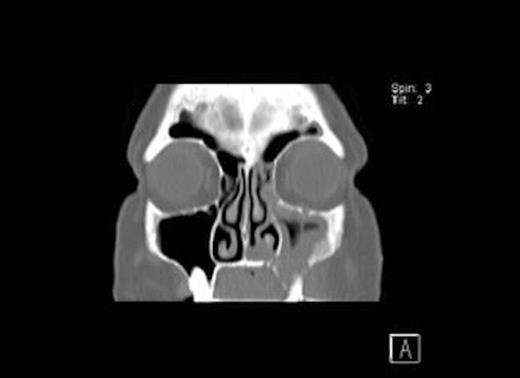

CT Scans (Fig. 1& 2) showed opacity and thickening of the left maxillary antrum with dehiscence of the medio-inferior and anterior walls of the sinus and a maxillo-oral fistula. There was destruction of bone in the floor of the left maxillary sinus consistent with an area of osteonecrosis secondary to bisphosphonate.

Axial CT Scan of the head showing osseo-sclerotic changes and defect in left maxillary sinus